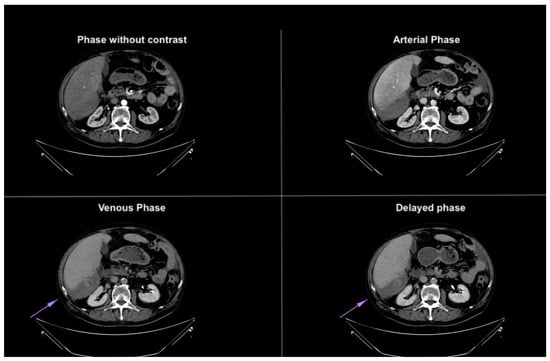

Figure 4. Axial CT images in different phases, highlighting extravasation of contrast medium within the subhepatic fluid collection. The extravasation becomes more prominent in the last phases, confirming the presence of active bleeding. The purple arrow demonstrates blood extravasation in the collection during the venous and delayed phases of the study, not visible in the baseline and arterial phases.